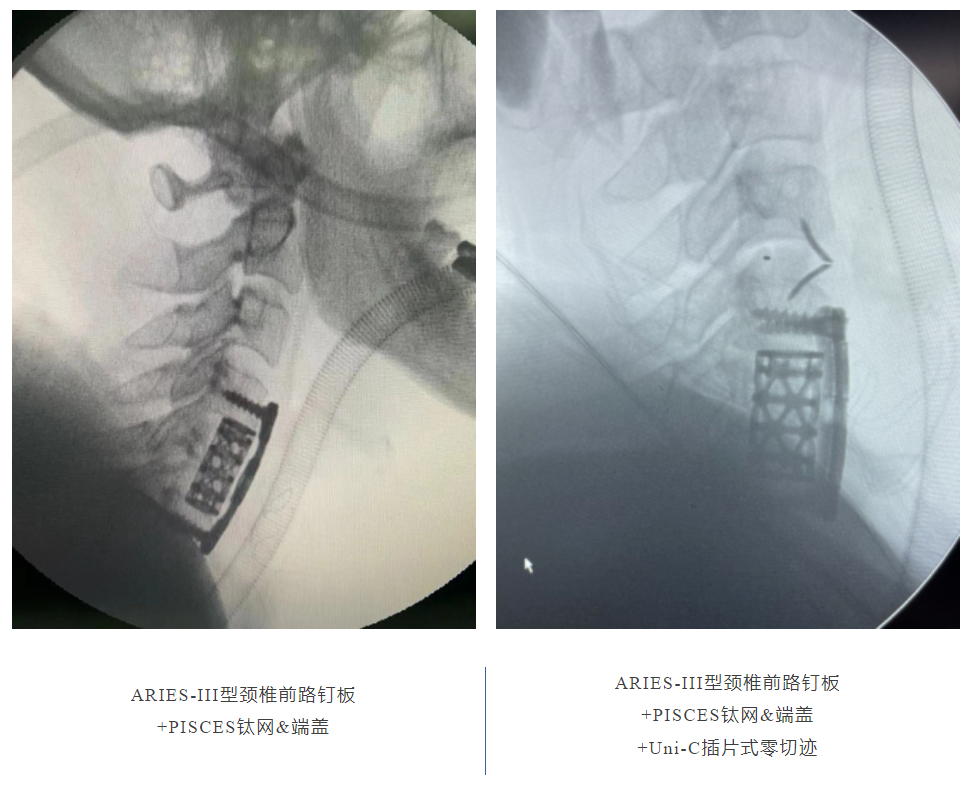

應(yīng)用效果展示: